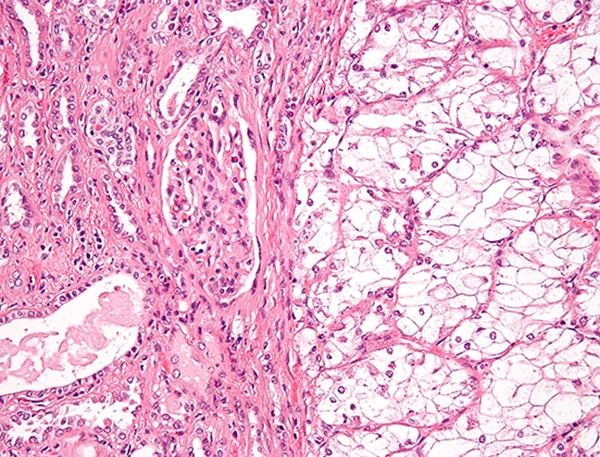

renal cell carcinoma

Renal cell carcinoma. Nephron, Wikimedia Commons

Renal cell carcinoma is a kidney cancer that originates in the lining of the proximal convoluted tubule, a part of the very small tubes in the kidney. It usually occurs in people between the ages of 60 and 70 and tends to be more common in males.